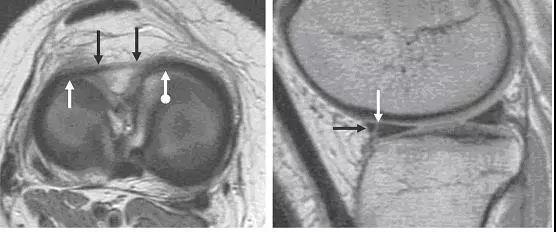

图 4 半月板横韧带

左图:横断面 T1 像显示半月板横韧带连接内侧半月板(白色圆箭头)和外侧半月板(白色直箭头)的前角;右图:经过半月板横韧带(黑色箭头)的矢状面,可见半月板横韧带与半月板前角之间的间隙呈现高信号(白色箭头),易误诊为半月板撕裂。